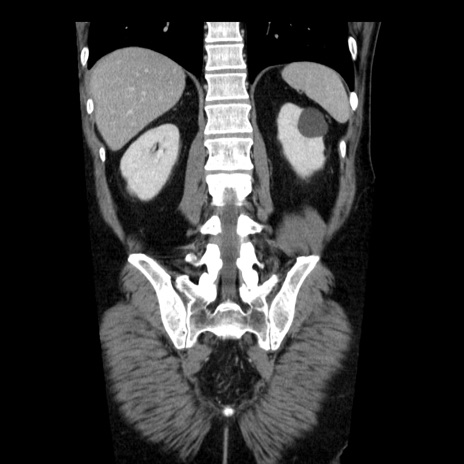

症例29(冠状断像)

【症例】40歳代男性

【現病歴】2日前から胃痛あり。徐々に周期的な激痛に変化した。本日になっても激痛があるため受診。

【身体所見】意識清明、BT 38-39℃台あり、腹部:膨満、やや硬、右下腹部に圧痛あり。

【データ】WBC 8500、CRP 23.26